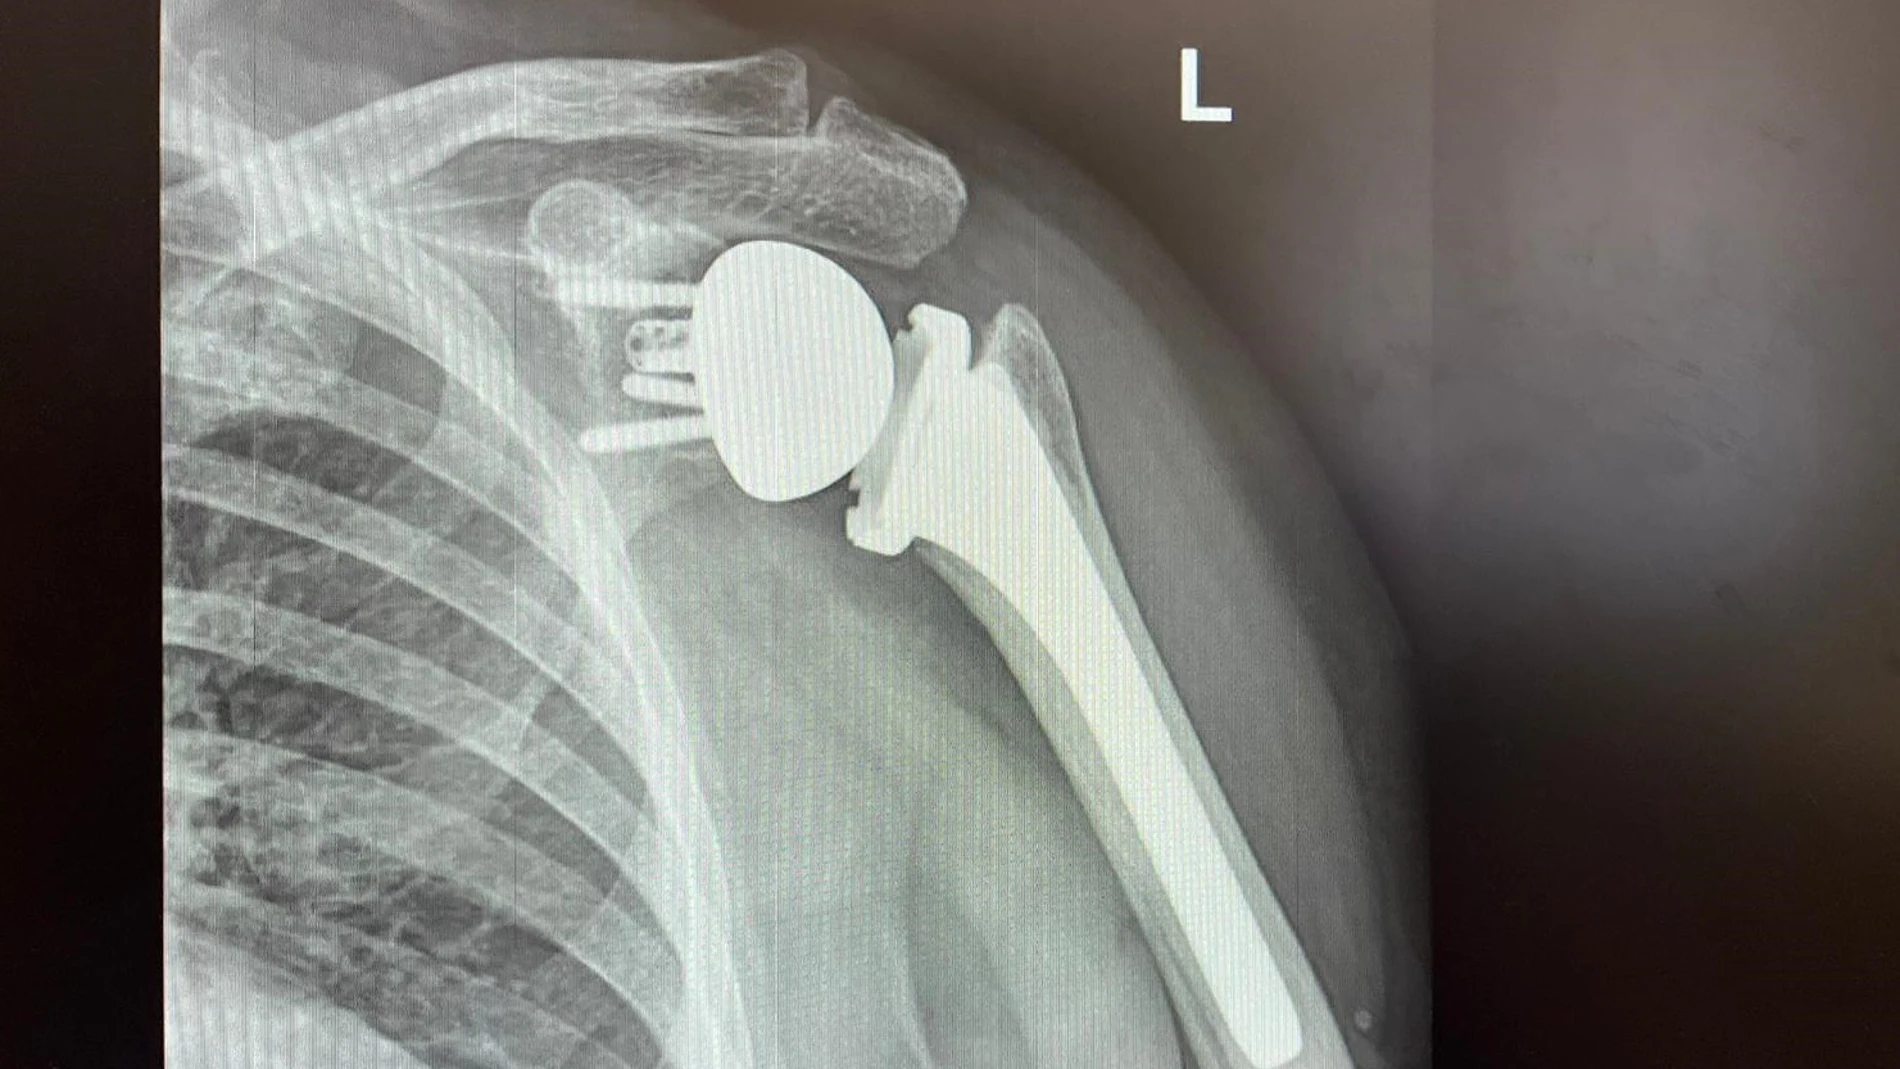

Así evolucionan las prótesis de hombro: se adaptan durante la cirugía y con tecnología 3D,.

Mejoran en movilidad, se colocan de manera más precisa y consiguen una mayor conservación del stock óseo,.

La cirugía del hombro es la que ha experimentado avances más importantes dentro del campo de la cirugía ortopédica en los últimos años. Así, a la generalización de técnicas quirúrgicas avanzadas, como la artroscopia, se ha sumado la evolución de las prótesis, consiguiendo mejorar de manera considerable la cirugía protésica de esta articulación.

El hombro es la articulación con más movilidad de nuestro cuerpo y, por tanto, el proceso de colocación de una prótesis se vuelve muy complejo, lo que va a exigir un equipo de cirujanos experimentado y una colaboración importante del paciente con el postoperatorio y la rehabilitación. Las prótesis de hombro, al igual que las de otras articulaciones como la cadera o la rodilla, son la opción para tratar varias patologías como la artrosis o la artritis, así como secuelas de una fractura o rotura de tendones y se colocan cuando el dolor y las limitaciones que sufre el paciente no mejoran con el tratamiento conservador. El objetivo de éstas es ofrecer una movilidad y funcionalidad prácticamente completa de la articulación del hombro y eliminar el dolor.

La introducción de las prótesis invertidas, que invierten la forma natural del hombro – la esfera se coloca en la glena y la forma cóncava en la cabeza humeral-, dio pie a solucionar los problemas que presentaban las prótesis anatómicas convencionales en los pacientes con rotura de manguito y supuso un gran paso en este campo. Sin embargo, actualmente, según destaca el doctor José Cárdenas, especialista en Traumatología y Cirugía Ortopédica del Hospital Quirónsalud Sagrado Corazón, los grandes avances se están dando en relación con la planificación y la navegación quirúrgica. “Estas nuevas formas de proceder previo a la cirugía y durante la misma nos facilita la tarea de colocación de la prótesis, pudiéndolo hacer de manera más precisa y consiguiendo una mayor conservación del stock óseo”, añade.

Para esta nueva forma de planificar, tal y como explica el doctor Cárdenas, se usa un sistema que permite descargar las imágenes de TAC del paciente en un programa informático, el cual realiza una perspectiva en 3D del hombro del paciente y facilita entender la configuración del mismo, pudiendo superponer los implantes en dicha reconstrucción. Esto permite poder elegir los implantes más adecuados para el paciente, y colocarlos en la posición más correcta, previamente a la cirugía, para minimizar complicaciones y proporcionar una mayor durabilidad de la prótesis.

“De lo que se trata es de conseguir unos resultados satisfactorios, más predecibles y controlados, individualizando el proceso quirúrgico a cada paciente”, apunta el doctor Cárdenas.

No obstante, no es solo una cuestión de planificación previa a la cirugía, sino que también todo esto se plasma durante el acto quirúrgico con la irrupción de las prótesis navegadas. Aunque no todas las prótesis son navegadas en la actualidad, el doctor Cárdenas explica que su funcionamiento se fundamenta en “utilizar una serie de sensores que se instalan en el paciente en la misma cirugía, y otros que existen en los instrumentales usados para la colocación de la prótesis, consiguiendo de esta manera reproducir lo que previamente se había valorado como óptimo en el programa informático durante la planificación”.

El doctor Cárdenas añade que, además de los avances en la planificación y la navegación, otro concepto importante de los modelos actuales de prótesis es su gran modularidad, así como la utilización de vástagos cortos o sin vástagos, un componente de la prótesis que se pone en el húmero y que, cuanto más pequeños sean, más conservación de hueso le permite hacer al cirujano. “Estas particularidades de las nuevas prótesis permiten variar el tipo de prótesis o adaptar sus componentes, según el estado de la articulación, en el mismo acto quirúrgico y en función de los hallazgos durante la cirugía”, concluye el doctor José Cárdenas.